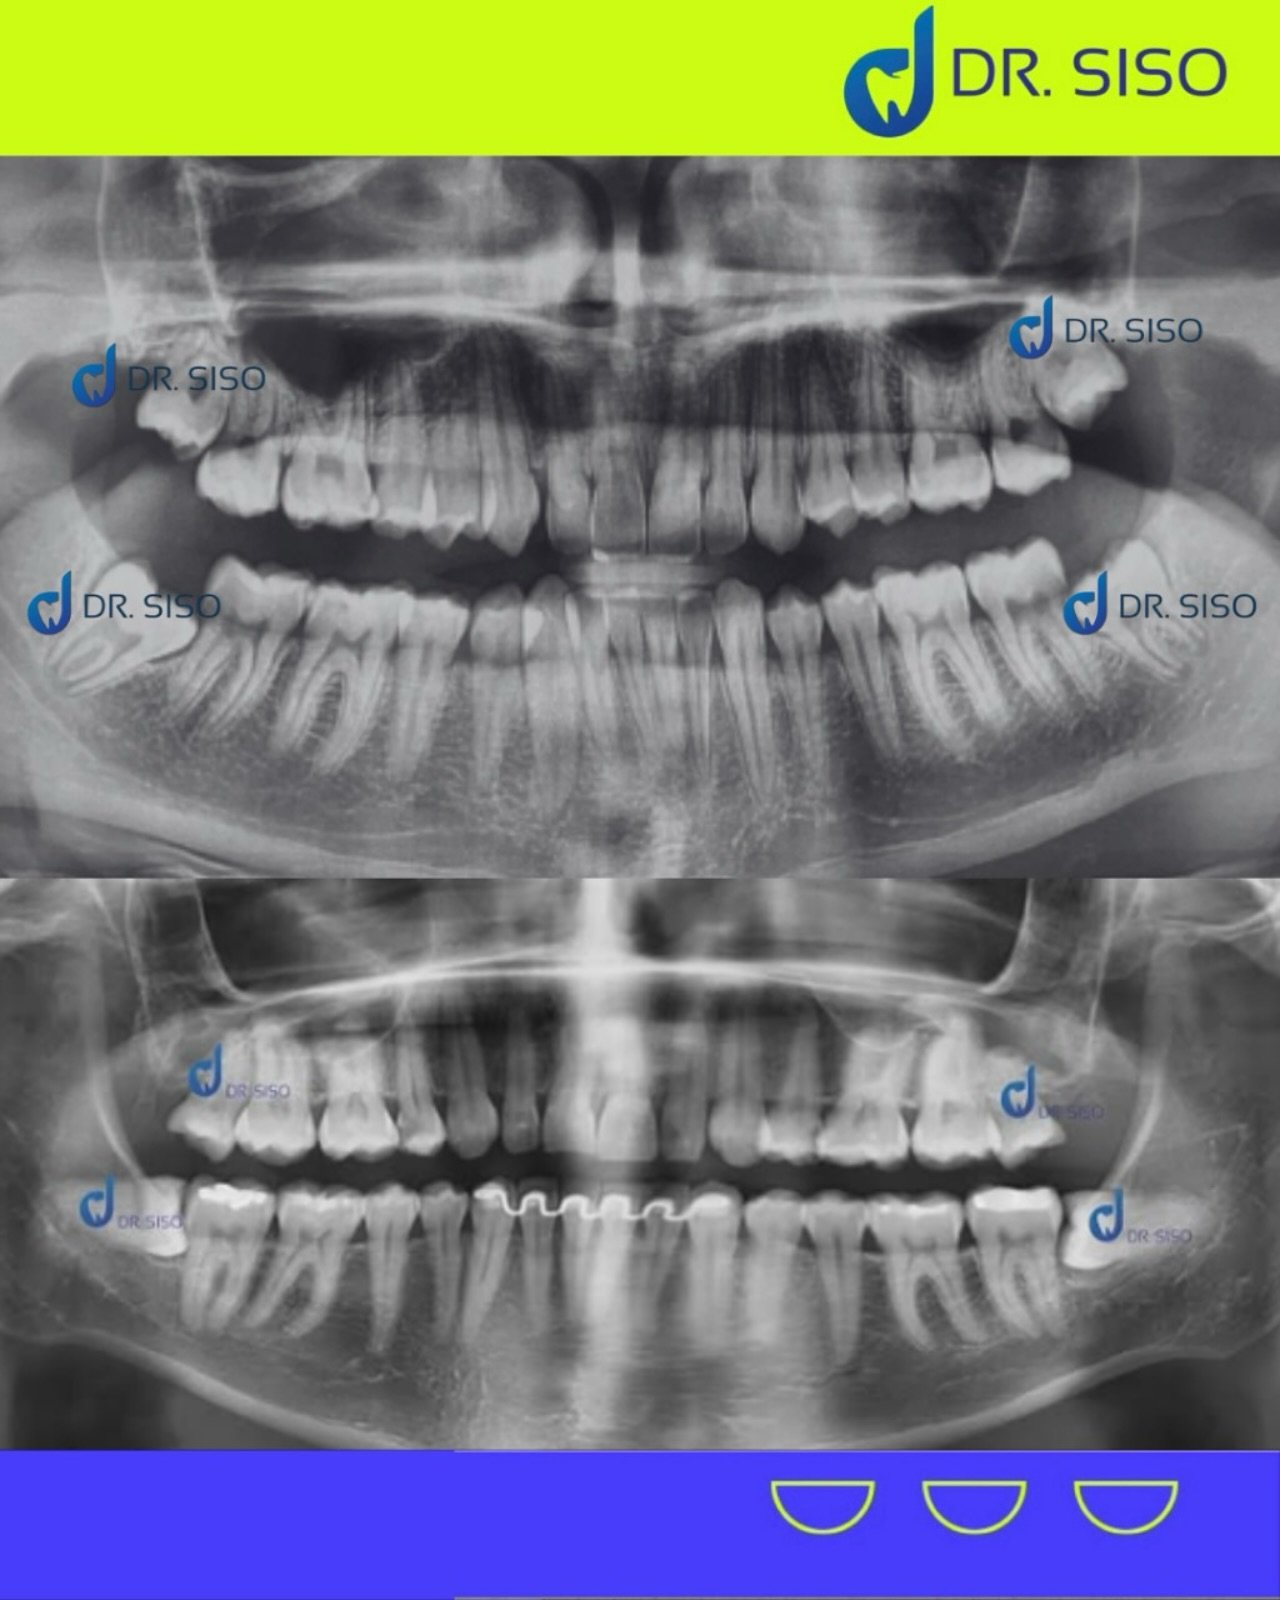

Sim, em muitos casos. Mesmo sem dor, o siso pode estar mal posicionado, pressionando outros dentes, causando reabsorção óssea ou prejudicando a mordida. A avaliação clínica e radiográfica é essencial para decidir com segurança.